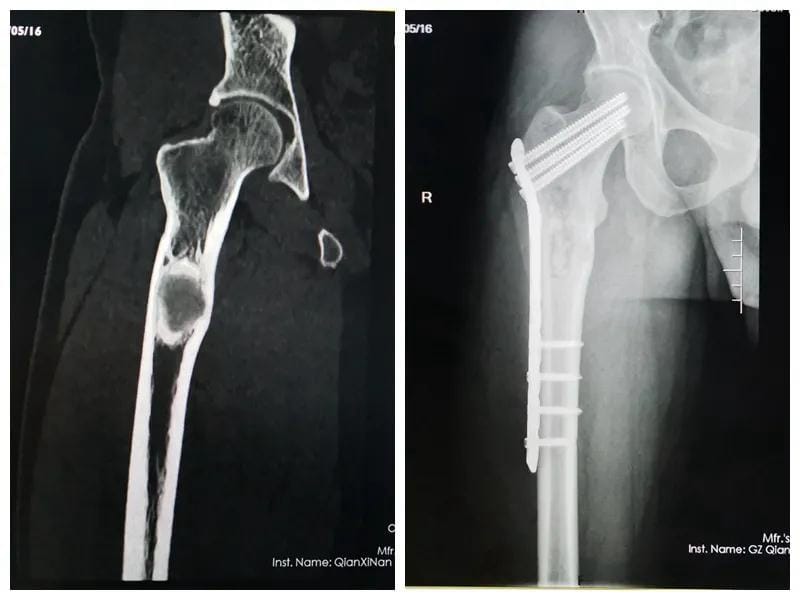

一位十七岁花季少女,因为足踝畸形长期卧床,患者曾先后到广州、昆明、贵阳等地众多知名医院就诊,给出的治疗方案均为截肢手术。家属抱着试试看的态度,到我院骨科门诊就诊,因病例特殊,科室医师经多次讨论,夜以继日设计治疗方案,在与病人及家属三方的共同努力下,通过三次矫形手术,让她终于站了起来,开始享受正常人的生活,不仅找到了工作,现在已经结婚生子,不久前还专程到科室向创伤骨科医护人员表达了谢意,看着她脸上洋溢的幸福,所有的医护人员在为她祝福的同时,也深感了“精治骨伤痛,共结续骨情”的精髓。

矫形、骨髓炎、骨肿瘤:Ilizarov肢体牵拉再生技术,骨延长、肢体延长,各类骨与软组织良恶肿瘤切除术,特别是经典骨巨细胞肿瘤刮除植骨骨水泥填充内固定术、四肢恶性骨肿瘤保肢术+新辅助化疗方案等标准化治疗等。